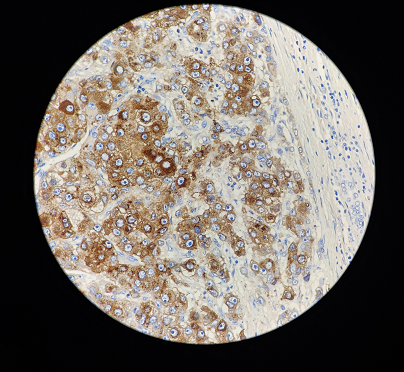

AFP(甲胎蛋白)抗体免疫组织化学染色,强度3+

AFP是在体液中发现的分子量为70KD的癌胚抗原,由胚胎卵黄细胞、胚胎肝细胞和胎儿肠道细胞合成的一种糖蛋白。主要用于标记低分化肝癌、胚胎性癌、卵黄囊瘤等生殖细胞肿瘤。细胞定位:细胞质